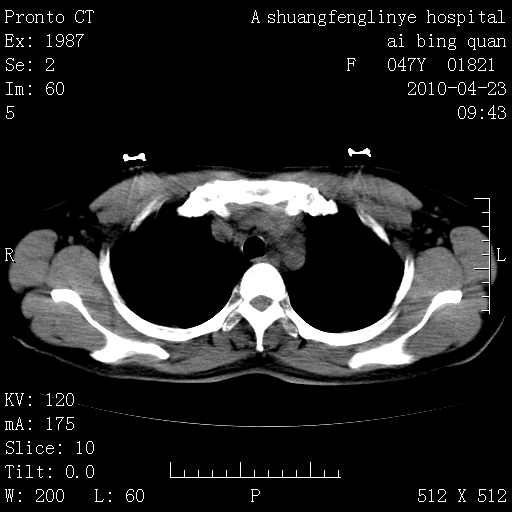

标题: CT25944:胸痛、气短、前几日高烧!肺Ca?请会诊! [打印本页]

标题: CT25944:胸痛、气短、前几日高烧!肺Ca?请会诊!

左侧乳腺低密度灶